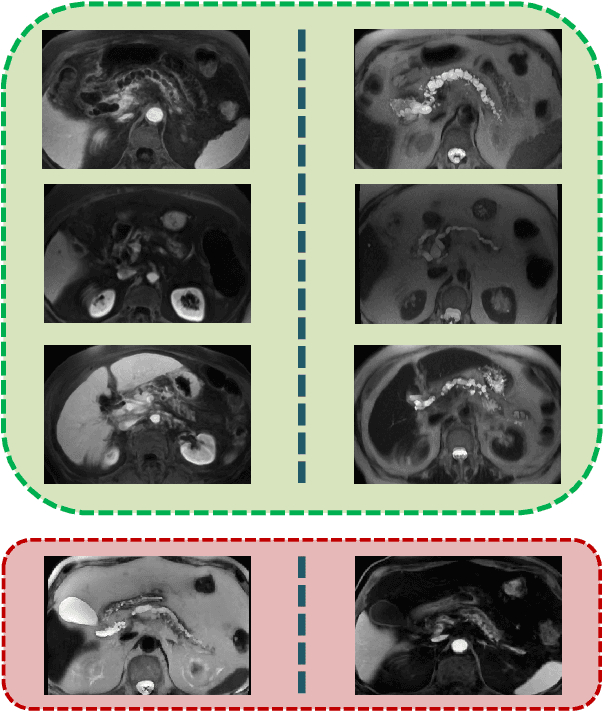

Abstract:Cancer is among the leading causes of death worldwide. Risk stratification of cancer tumors in radiology images can be improved with computer-aided diagnosis (CAD) tools which can be made faster and more accurate. Tumor characterization through CADs can enable non-invasive cancer staging and prognosis, and foster personalized treatment planning as a part of precision medicine. In this study, we propose both supervised and unsupervised machine learning strategies to improve tumor characterization. Our first approach is based on supervised learning for which we demonstrate significant gains in deep learning algorithms, particularly by utilizing a 3D Convolutional Neural Network along with transfer learning. Motivated by the radiologists' interpretations of the scans, we then show how to incorporate task dependent feature representations into a CAD system via a "graph-regularized sparse Multi-Task Learning (MTL)" framework. In the second approach, we explore an unsupervised scheme to address the limited availability of labeled training data, a common problem in medical imaging applications. Inspired by learning from label proportion (LLP) approaches, we propose a new algorithm, proportion-SVM, to characterize tumor types. We also seek the answer to the fundamental question about the goodness of "deep features" for unsupervised tumor classification. We evaluate our proposed approaches (both supervised and unsupervised) on two different tumor diagnosis challenges: lung and pancreas with 1018 CT and 171 MRI scans respectively.

Abstract:Pancreatic cancer has the poorest prognosis among all cancer types. Intraductal Papillary Mucinous Neoplasms (IPMNs) are radiographically identifiable precursors to pancreatic cancer; hence, early detection and precise risk assessment of IPMN are vital. In this work, we propose a Convolutional Neural Network (CNN) based computer aided diagnosis (CAD) system to perform IPMN diagnosis and risk assessment by utilizing multi-modal MRI. In our proposed approach, we use minimum and maximum intensity projections to ease the annotation variations among different slices and type of MRIs. Then, we present a CNN to obtain deep feature representation corresponding to each MRI modality (T1-weighted and T2-weighted). At the final step, we employ canonical correlation analysis (CCA) to perform a fusion operation at the feature level, leading to discriminative canonical correlation features. Extracted features are used for classification. Our results indicate significant improvements over other potential approaches to solve this important problem. The proposed approach doesn't require explicit sample balancing in cases of imbalance between positive and negative examples. To the best of our knowledge, our study is the first to automatically diagnose IPMN using multi-modal MRI.